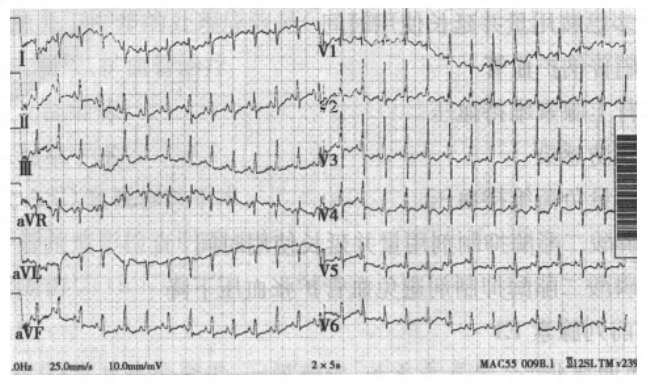

- [材料题] 患儿,女性,5岁,因“发现心脏杂音2个月余”来入院。患儿在2个月前因“感冒、肺炎”在当地医院治疗,查体发现心脏杂音,未做进一步检查。平素活动可,无紫绀、晕厥史。体重及身高发育较同龄儿童稍差,易感冒。入院体查:体重14kg;心率128次/分,心律整齐。胸骨左缘2~3肋间闻及3/6级吹风样收缩期杂音,肺动脉区第二心音亢进并有固定分裂。唇甲无紫绀。 患儿心电图见下图;超声心动图报告:房间隔下腔侧回声中断约13mm,右下肺静脉引流入右房。

- 简答题1、患儿心电图的诊断为?